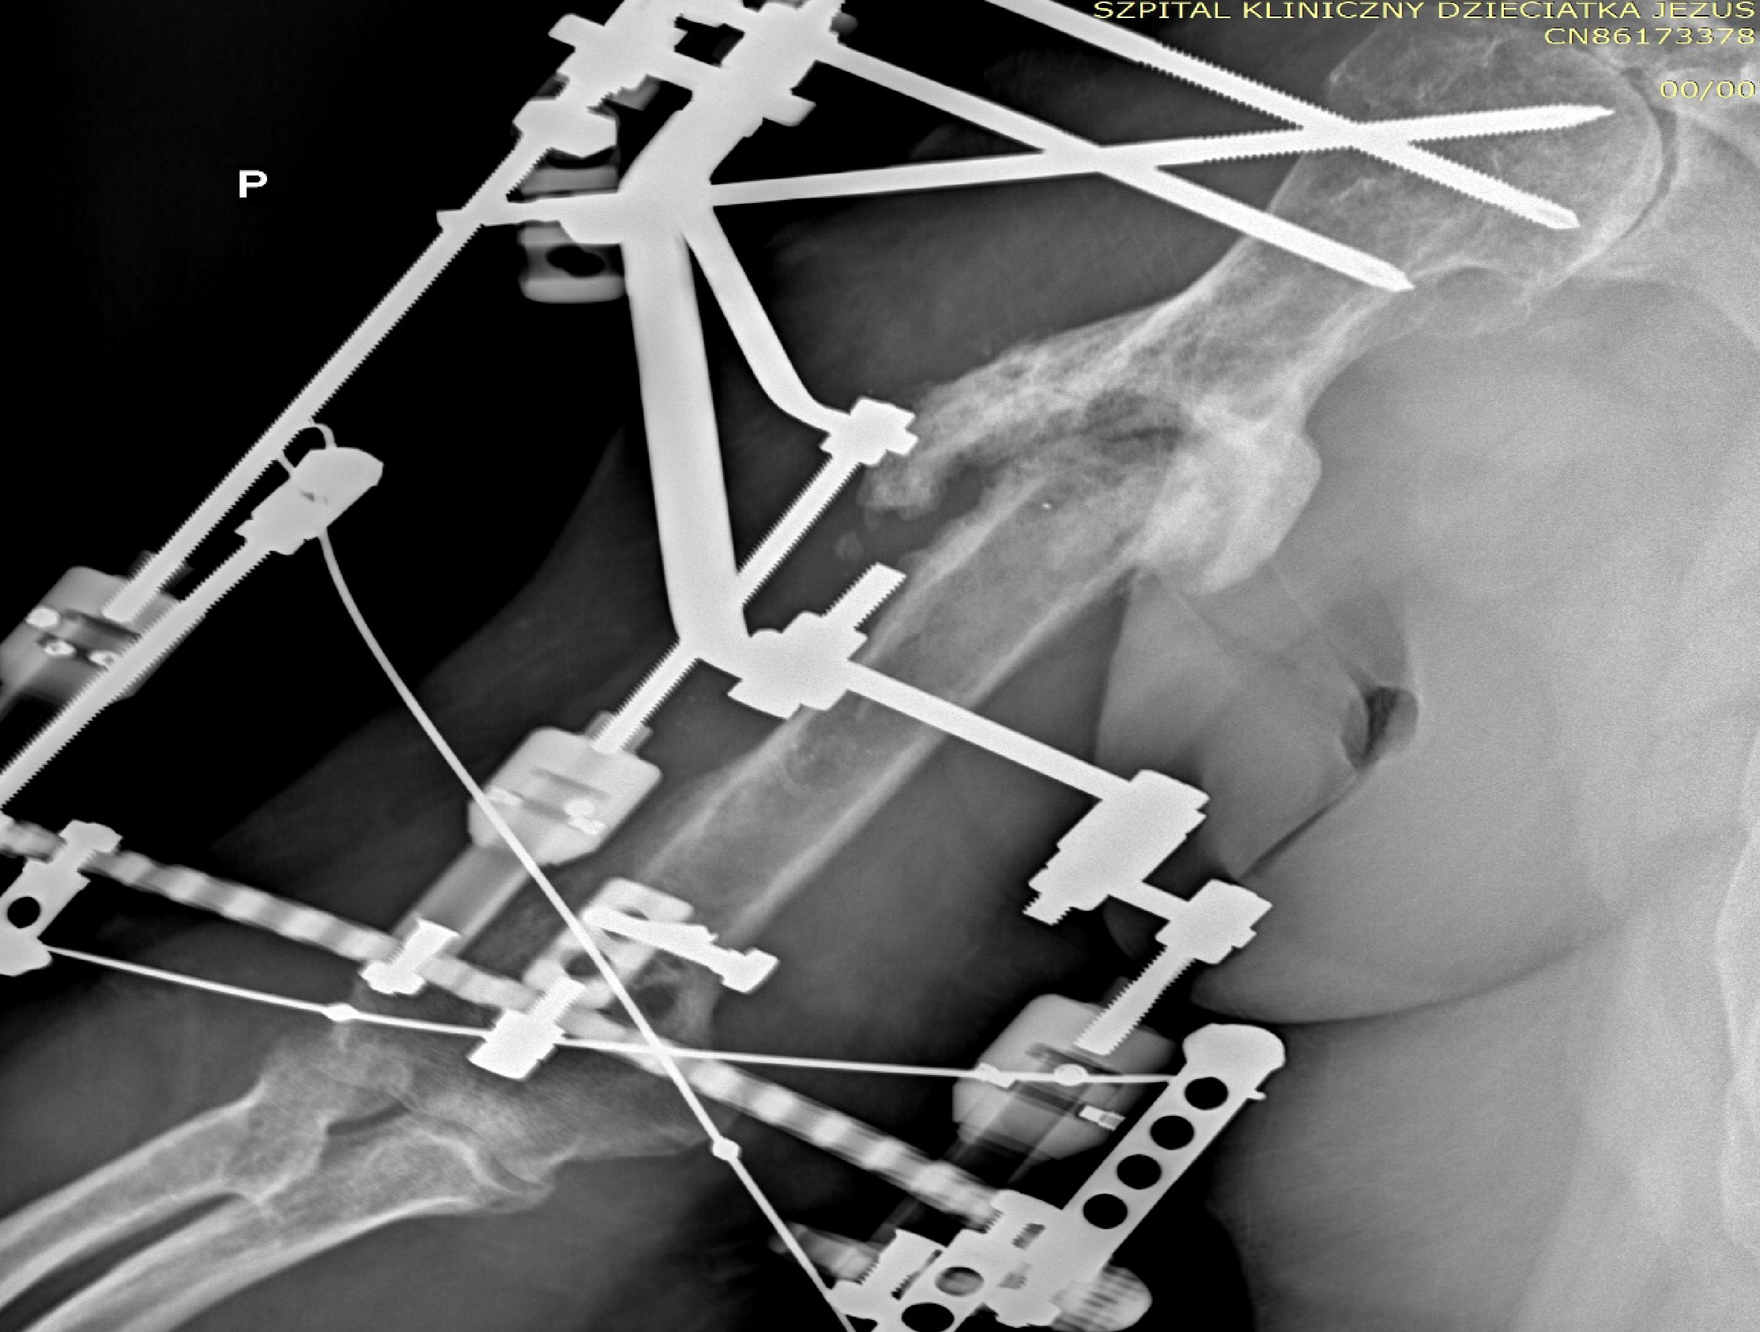

Hypertrophic nonunion of the humeral shaft treated with Ilizarov external fixator.

From: Comparison of surgical techniques for the treatment of humeral nonunion using the Ilizarov method